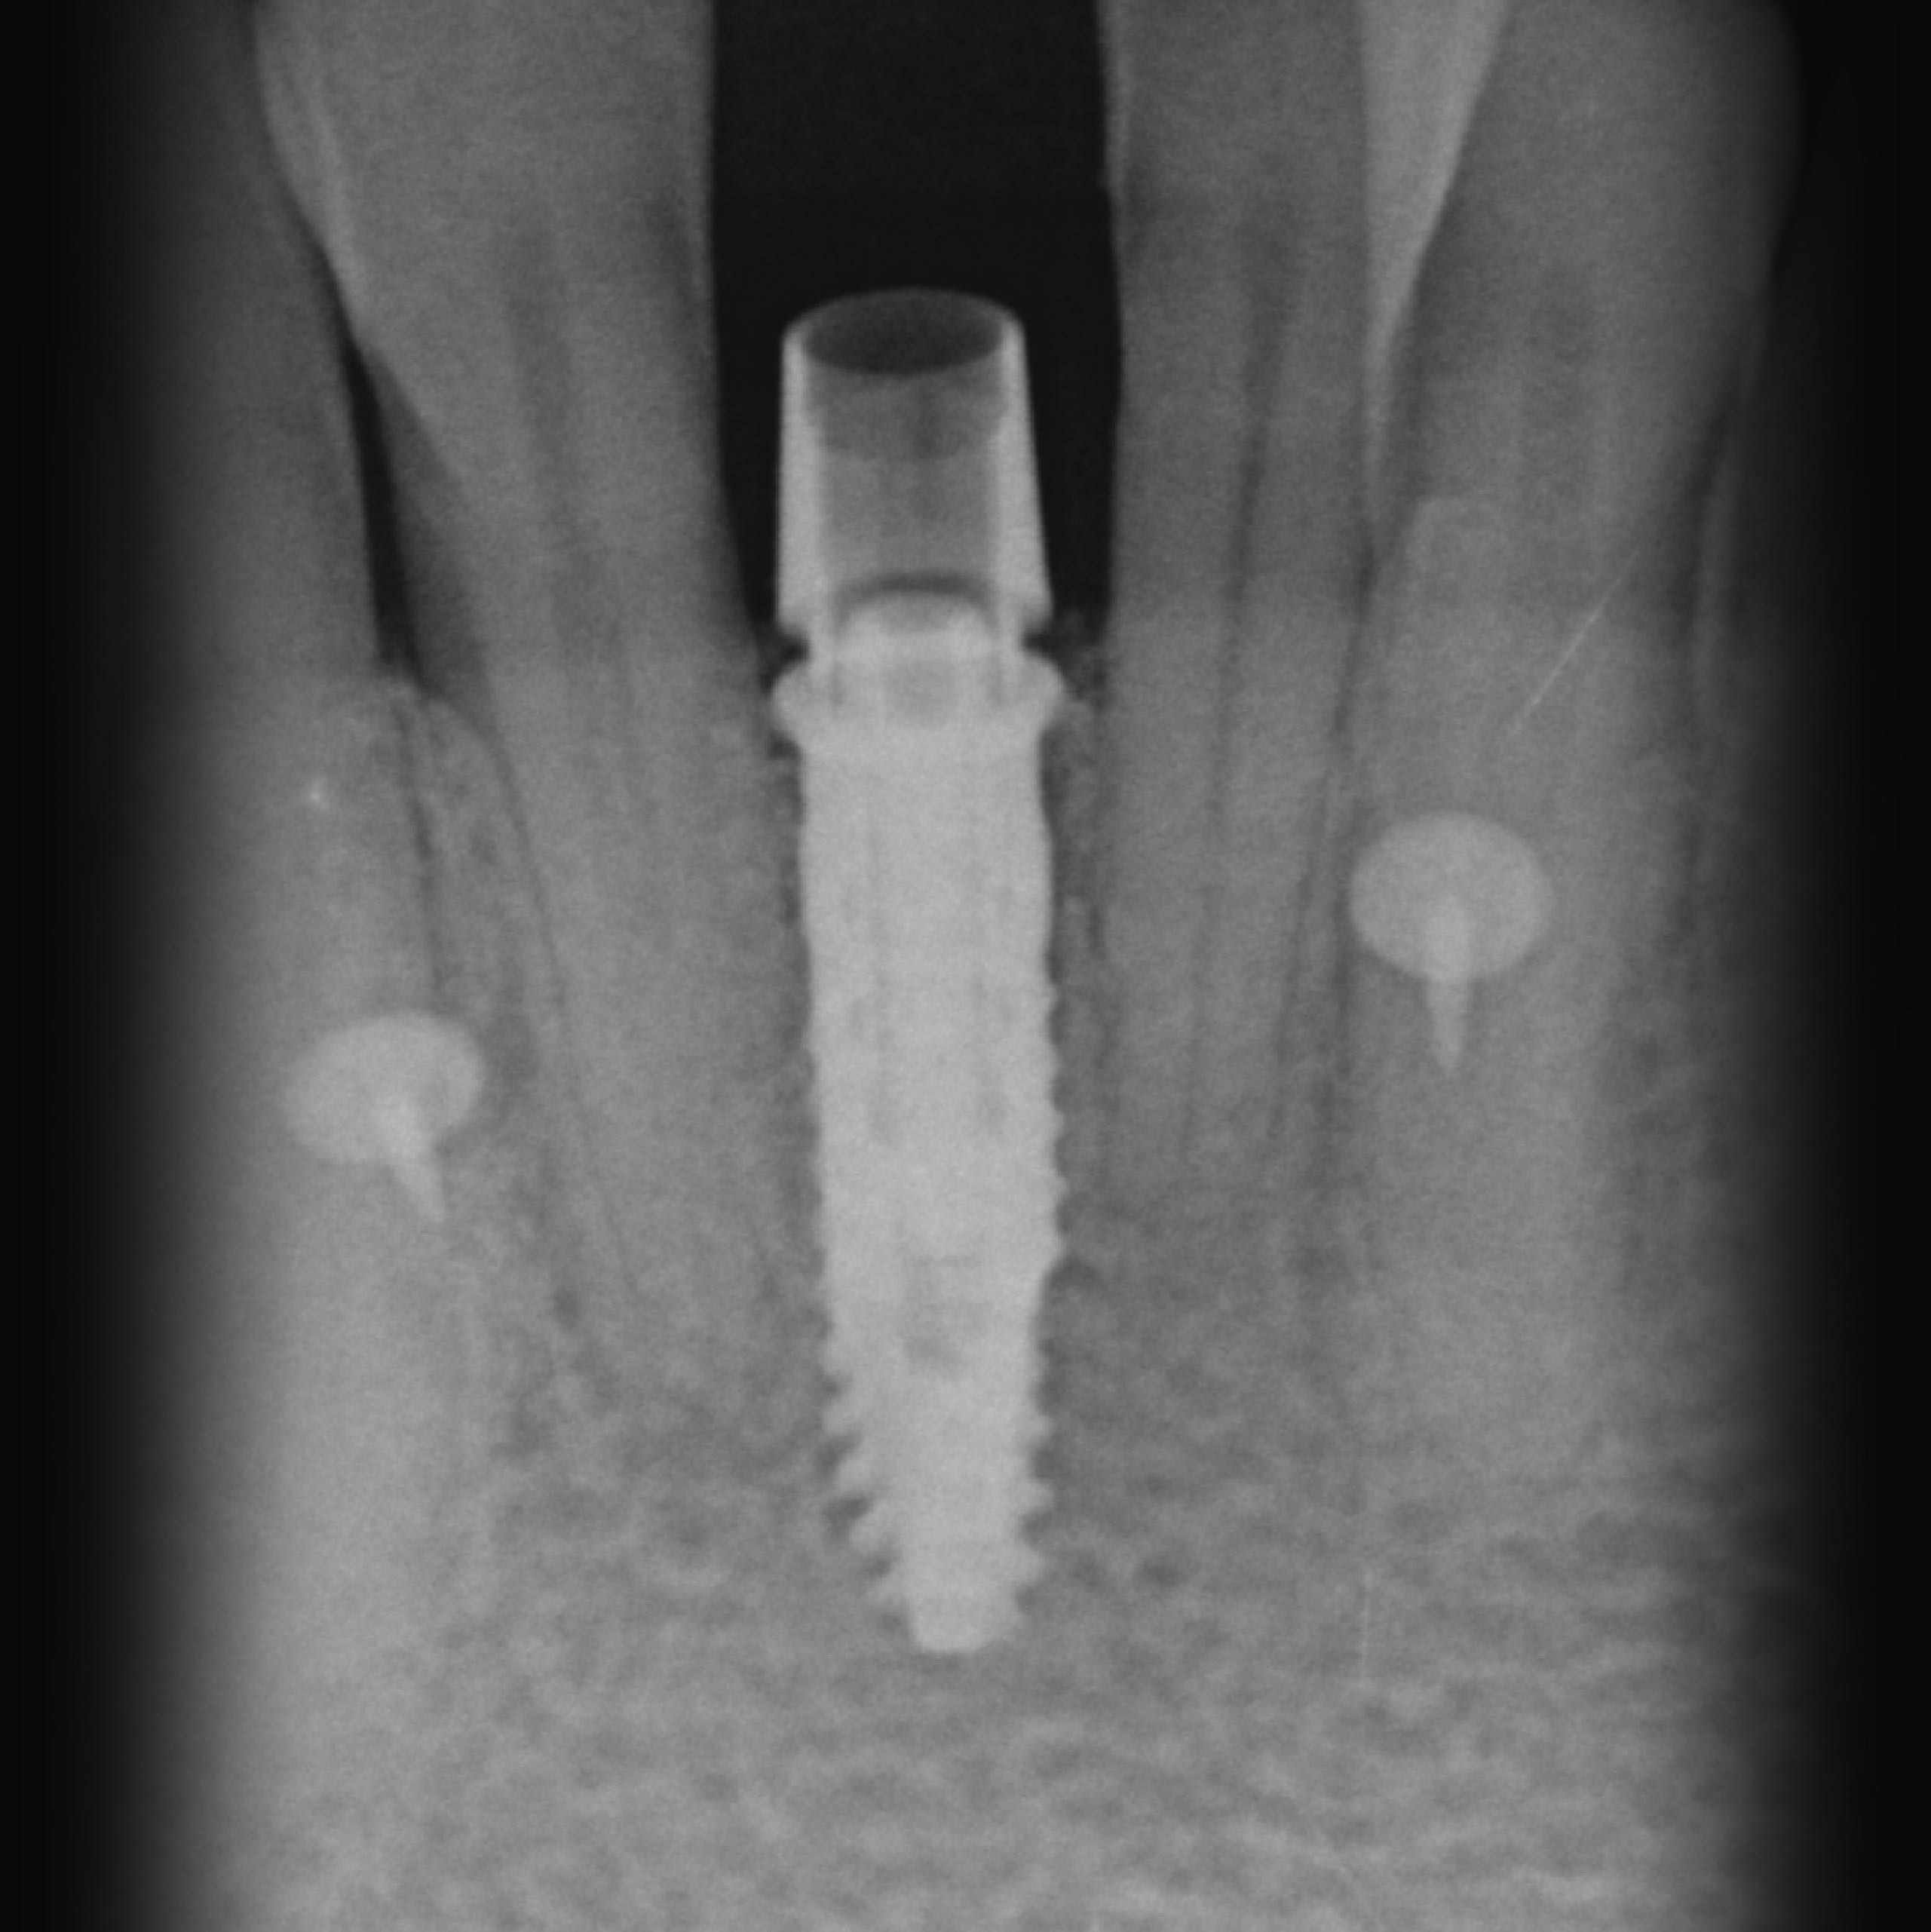

Durch die Vorbehandlungen waren schon ausgeprägte Schäden an den Weichteilen und Knochen vorhanden. Besondere Schwierigkeiten waren in diesem Fall die engen Platzverhältnisse und der schon stark geschädigt und abgebaute Knochen.

Bei Behandlungsbeginn

• Fehlender Unterkieferfrontzahn

• Sehr enge Platzverhältnisse

• Verschachtelt stehende Zähne

• Zahnentfernung

• Knochen- und Weichgewebeaufbau

• Implantation

• Freilegung und provisorische Versorgung

• Endgültige Krone

11/2019

Knochenaufbau

• 0/2020

Implantation